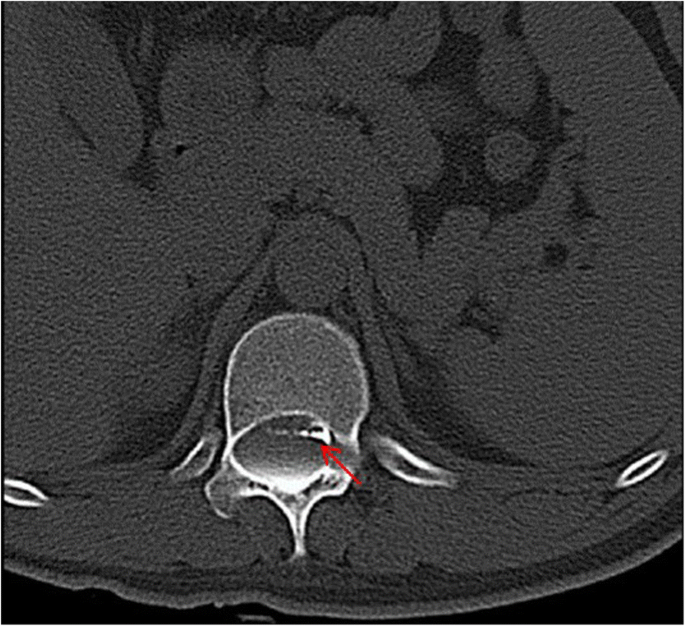

This is a 26-year-old man who experienced right lower limb weakness for 2 years and the weakness exacerbated in last half year. He visited the second affiliate hospital of the Zhejiang University School of Medicine. A physical examination indicated the result of the straight leg raising test was positive and also muscle atrophy. The muscle power of the right lower limb had decreased to grade 3. There was no sensory impairment. Magnetic resonance imaging revealed an intraspinal extradural tumor over T10 to L3 (Fig. 1). It appeared to be a spinal extradural arachnoid cyst (SEAC). To confirm whether the fistula existed between the subarachnoid space and arachnoid cyst, and to localize the position of the fistula, we performed a real-time technique. First, we injected contrast medium into the cyst under fluoroscopy. After 1 h the follow-up computed tomography (CT) was administered, and it revealed there was no contrast-infiltration into the subarachnoid space (Fig. 2). We then extracted about 20 mL of fluid from the cyst. The follow-up magnetic resonance imaging on the same day indicated the cyst did not become smaller (Fig. 3). A “one-way valve” fistula was suspected such that cerebral spinal fluid could pass into the cystic space from the subarachnoid space but could not flow in the opposite manner. Therefore we designed a procedure to localize the fistula. We penetrated two needles into the cyst and subarachnoid space separately in the L3/L4 level under digital subtraction angiography (Fig. 4). Pending the fluid drained through those two needles, we injected 10 mL of contrast medium slowly into the subarachnoid space and a little contrast medium infiltrated into the cystic space horizontally at the T12/L1 level. We then administered high resolution computed tomography (HRCT) immediately to confirm the position in the axial plane. The HRCT revealed a funnel-shaped enhancement between the lower edges of the T12 body and the left nerve root, and this is the accurate position of the fistula (Fig. 5).